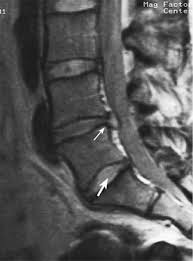

تشخیص

با مراجعه بیماران به کلینیک درد و معاینه دقیق صورت میگیرد.شایعترین وسیله تایید این تشخیص انجام MRI میباشد.